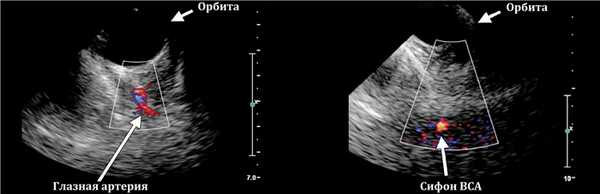

Орбитальный доступ через верхнее веко при закрытых глазах пациента; можно видеть глазную артерию и поперечный срез сифона ВСА.

![]()